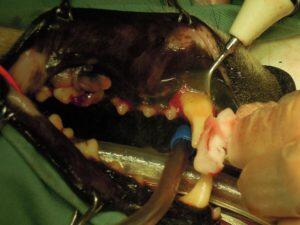

4.炎症性エプリスを疑い、スケーリングを行ってから

5.腫瘤を深い場所から切除し、

6.歯肉の形成を行い縫合し

7.保存が困難な歯は抜歯を行い

8.周囲の炎症した部位を切除して

9.抜歯した部位を縫合しました。